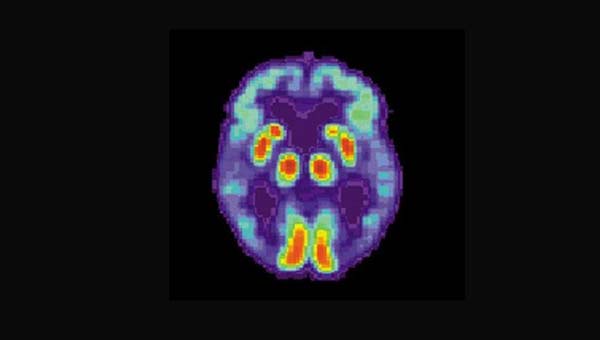

Ниже на картинке позитронно-эмиссионной томографией отсканированы эмоциональные зоны мозга при болезни Альцгеймера, демонстрирующие угасание их активности.